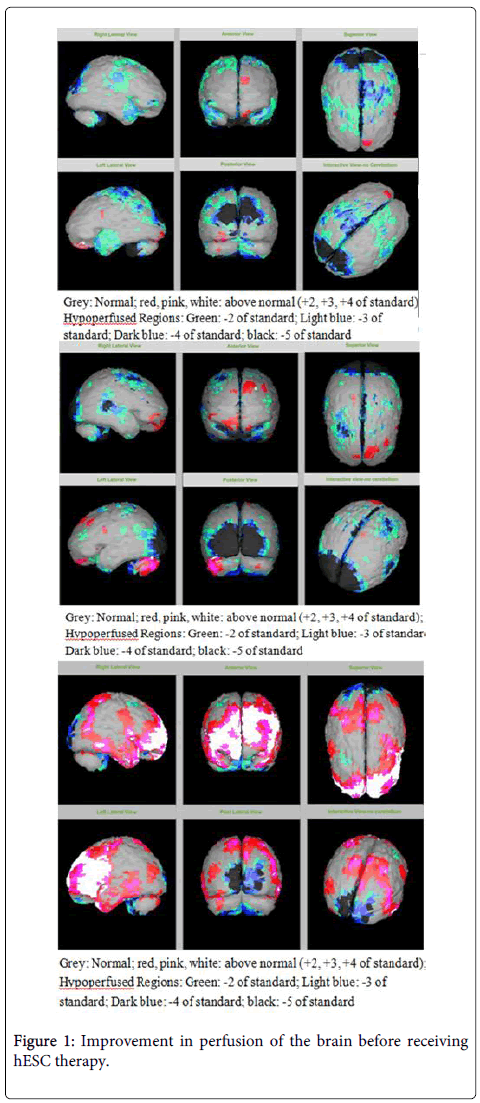

該患者的SPECT掃描如圖1和2所示。

SPECT掃描

在研究開始和結(jié)束時,23名患者接受了SPECT掃描。在枕葉或額葉或雙葉中觀察到灌注不足。23例接受SPECT掃描的患者中,5例患者表現(xiàn)為枕葉灌注不足,7例患者表現(xiàn)為額葉灌注不足,11例患者表現(xiàn)為枕葉和額葉灌注不足。

總體而言,治療結(jié)束時,2名患者的灌注正常,18名患者(12名男性和6名女性患者)顯示灌注顯著改善(>60%),3名患者顯示灌注中度改善(30-60%)。大多數(shù)在接受hESC治療前額葉和枕葉嚴重低灌注的患者在接受 hESC 治療后情況有所改善。23名可獲得SPECT掃描報告的患者的GMFCS評分在hESC治療后有所改善(表2)。

眾所周知,神經(jīng)干細胞可以通過重新填充受損區(qū)域并防止細胞進一步退化來恢復正常視力。hESC通過增殖成相似的細胞類型來啟動受損細胞的再生。在本研究中觀察到灌注改善,這反映在SPECT掃描中。詹森等人研究顯示,一名5歲腦癱患者在接受臍帶血干細胞治療2個月后視力有所改善。